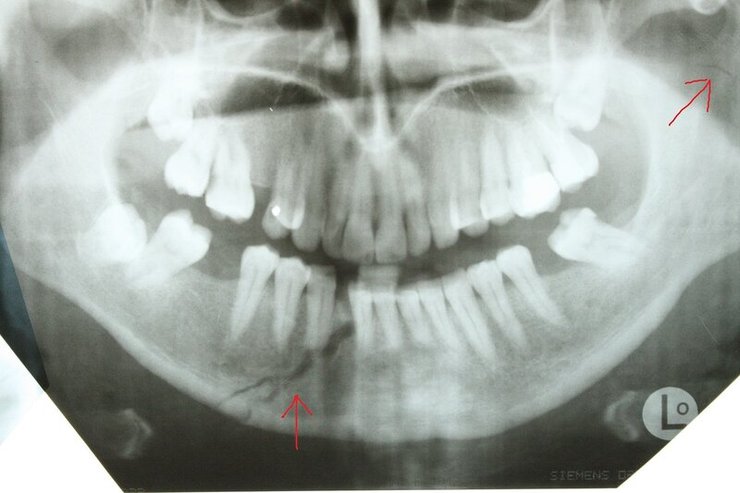

Сын главы Чечни Рамзана Кадырова Адам Кадыров мог сломать челюсть, когда попал в ДТП. Кроме этого, он имеет еще ряд менее значительных травм.

Авторы отмечают, что характерный для такой травмы отек лица спадает лишь через 1-2 недели. А на то, чтобы снять фиксацию челюсти, понадобится примерно месяц.

Сломанная в результате ДТП челюсть Адама Кадырова сломана в результате ДТП Челюсть Адама Кадырова NIYSO

Также в результате аварии у Кадырова-младшего могли появиться рваные раны, рассечения, разрывы кожи и гематомы. Из-за этого может понадобиться еще несколько недель, чтобы скрыть последствия аварии.